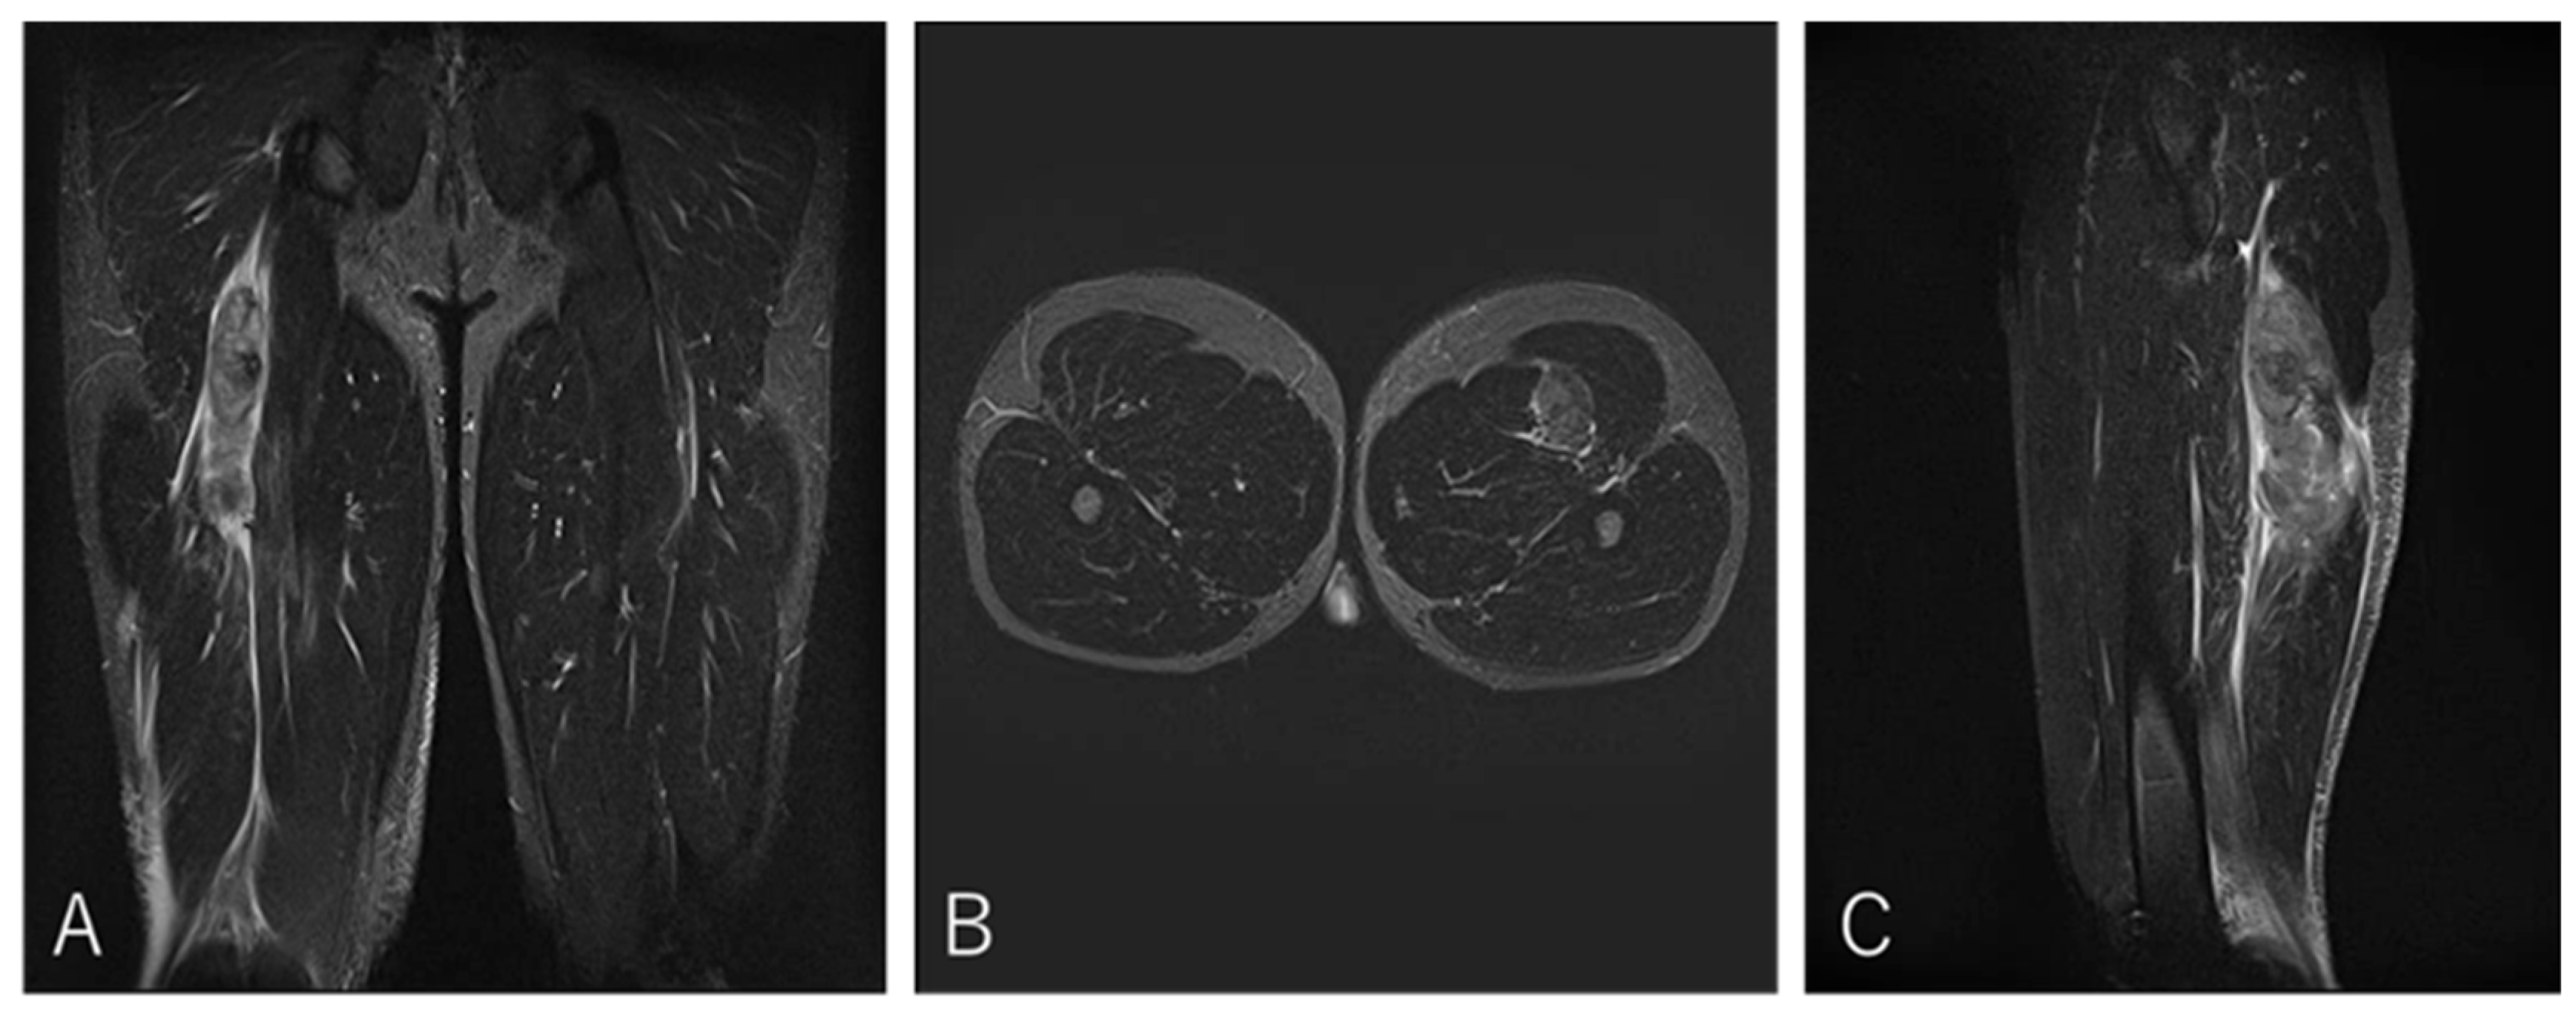

3.4.4. Case 4—Type II/Zone C (Proximal MTJ Tear), Grade 2

A 20-year-old center (BK) developed posterior thigh pain during a match while tackling an opponent. He returned to play after three weeks (Figure 7).

Figure 7. Case 4 MRI images: BFLH proximal MTJ injury, Type II. (A) (Coronal image): This is an injury to the proximal musculotendinous junction of the CT, with no evidence of tendon tortuosity. Haemorrhage is present on the BFLH side. (B) (Axial image): prone position, A haematoma is noted on the BFLH side of the CT. (C) (Sagittal image): A haematoma is observed in the cross-section of the BFLH.